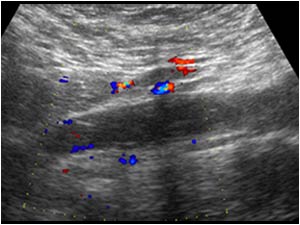

Huyết khối TM chủ dưới

Huyết khối TM chủ dưới - Ảnh 3

» Thông tin: Nữ giới – 68 tuổi.

» Lâm sàng: Sưng phù chi dưới.